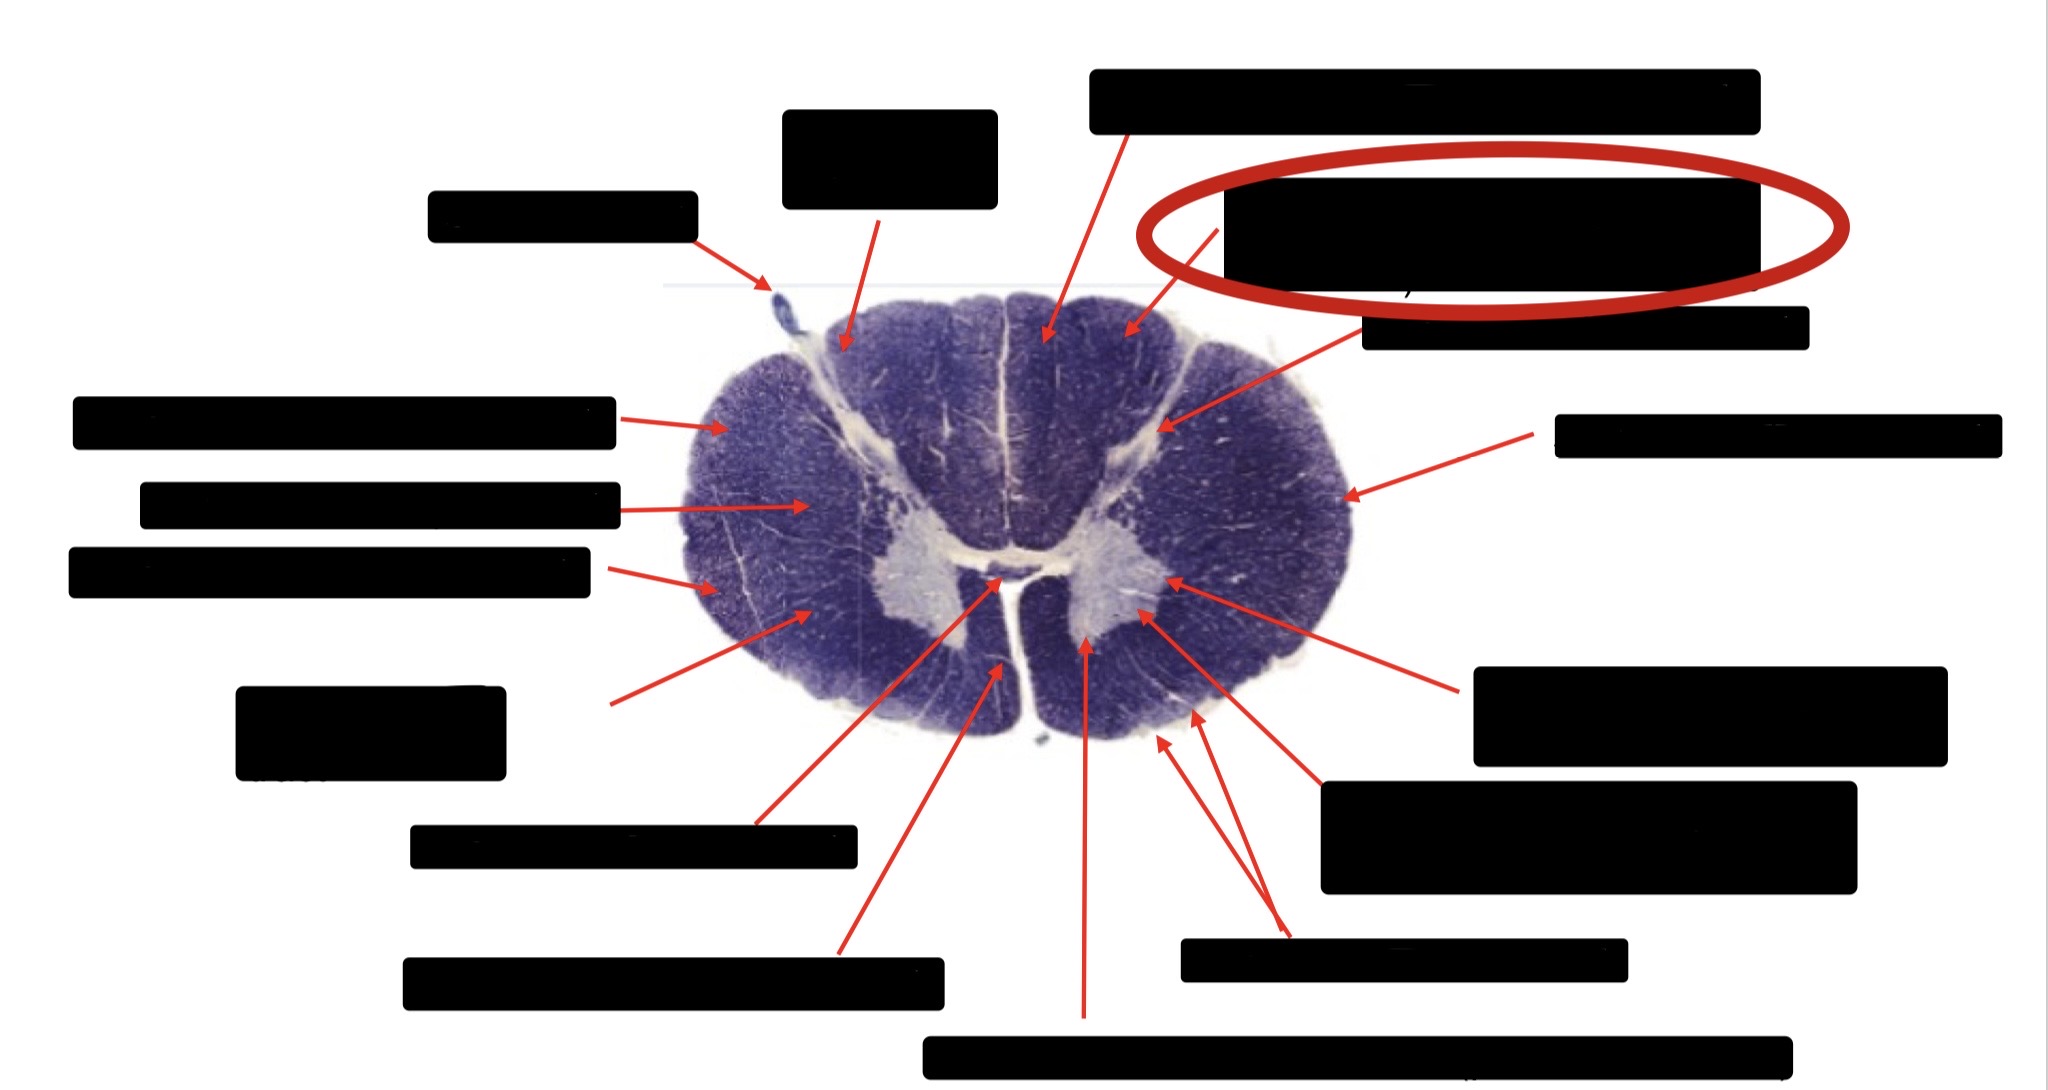

Posterior Column (Fasciculus Gracilis)

Spinothalmic Tract

Posterior Column (Fasciculus Cuneatus)

Substantia Gelatinosa

Anterior Horn Motor Neurons (Distal Muscles)

Anterior Horn Motor Neurons (Proximal Muscles)

Ventral Root Fibers

Central Canal

Anterior Corticospinal Tract

Large Fiber Entry Zone

Dorsal Rootlet

Posterior Spinocerebellar Tract

Lateral Corticospinal Tract

Anterior Spinocerebellar Tract

Accessory Nerve Fibers

Anterior Horn Motor Fibers (Accessory Muscles)

Anterior Horn Motor Fibers (Proximal Muscles)

Anterior Horn Motors Neurons (Proximal Muscles)